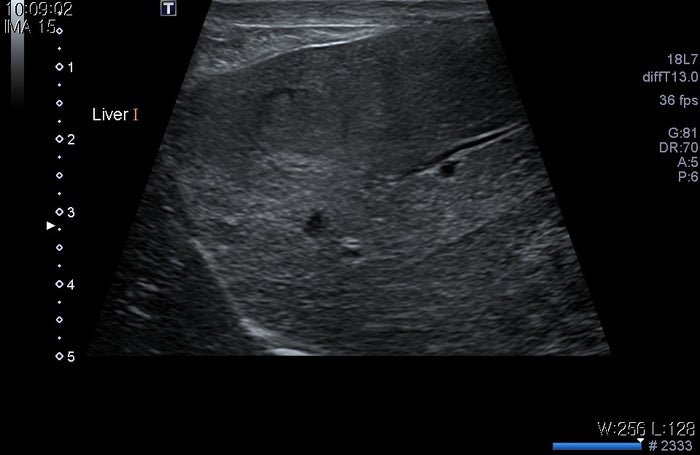

지금부터는 애완동물의 간종양에 대해 말씀드리겠습니다.오늘 얘가 보인 증상이 뭐였을까요?증상 : 구토, 최근 구토가 심하여 동물병원에 내원하게 된 아이입니다.아이가 구토하는 원인을 찾기 위해 검진을 하던 중 종괴가 발견되었습니다.지금까지는 위장관 관련 진료만 받았대요.오늘은 좀 더 자세한 검사를 해봤습니다.강아지 간종양 검사 간종양 검사는 1차적으로 초음파를 통해 확인할 수 있으며, 간종양으로 의심되는 정황이 발견되면 이후 CT 촬영을 하여 종양 전이 평가와 주변 조직과 유착되거나 침습되지 않았는지 확인해야 합니다.그래서 얘도 CT 검사를 했는데 CT 검사 결과

간에서 2개의 종괴가, 관찰 간에서 2개의 종괴가 관찰되었습니다.1. 좌횡격막에 가까운 위치(좌외엽 또는 내엽으로 추정)와 2. 위에 가까운 위치(좌외엽으로 추정)에 각각 1개씩 관찰되었습니다.

간종류의 크기 간종류의 크기는 1. 횡격막에 가까운 위치 약 2.17cm * 2.07cm * 2.06cm 2.위에서 가까운 위치 약 4.55cm * 3.25cm * 4.31cm 정도의 크기로 확인됩니다.위에 가까운 위치의 종괴는 소만곡과 매우 인접해 있어 유착 가능성도 배제할 수 없었습니다.반려동물의 간종양은 어디에 발생할까.이렇게 간은 여러 개의 잎으로 나뉘어져 있는데 이 여러 개의 간엽 중 어디에나 종양이 발생할 수 있습니다.얘는 두 군데서 발생했어요.애견간종양 치료방법→수술